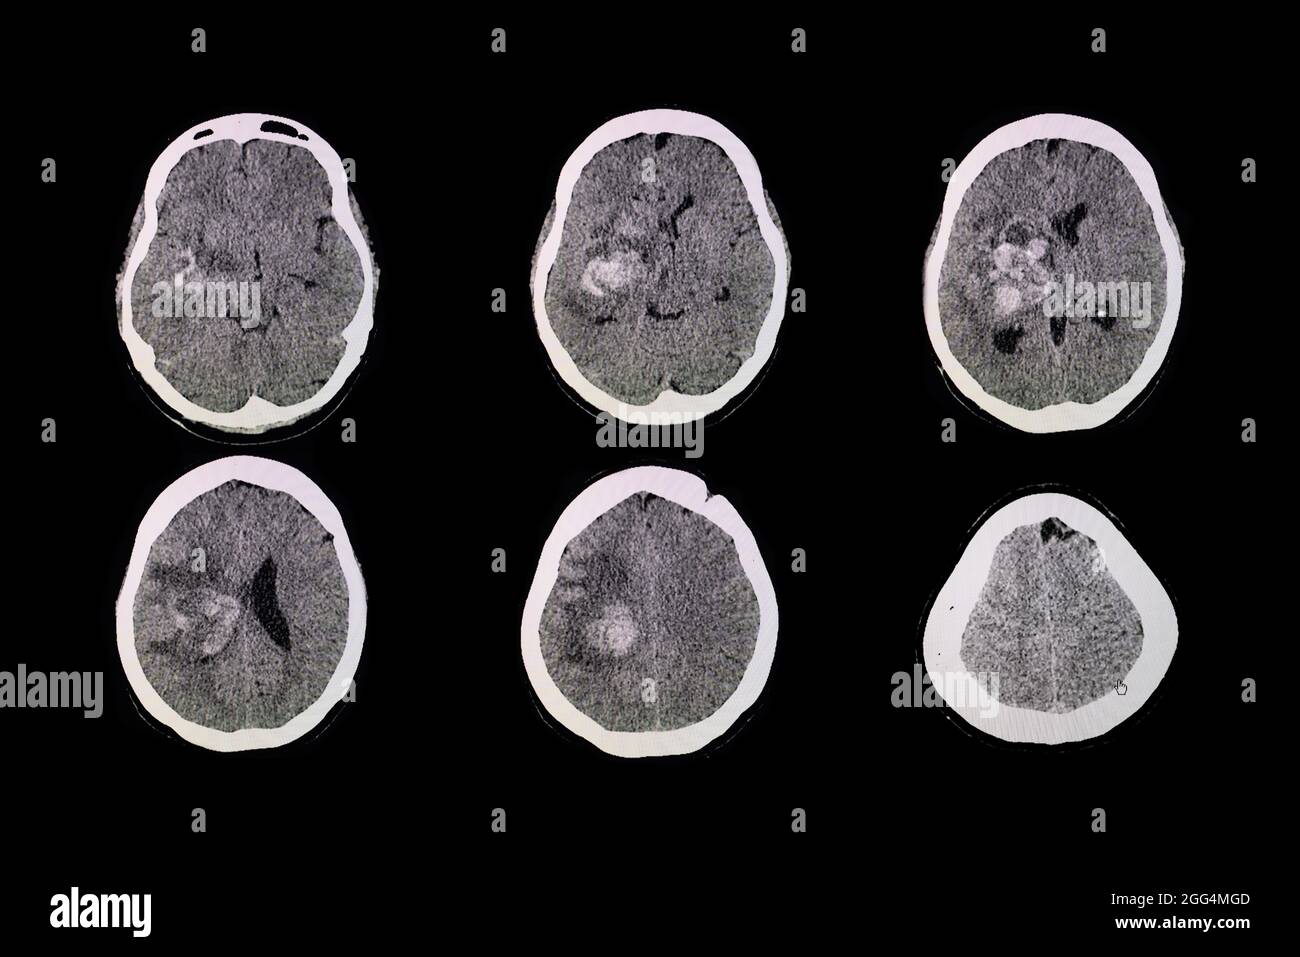

Scanner du cerveau du patient avec une hémorragie et un hématome au niveau de la ganglion basal droit. Banque D'Imageshttps://www.alamyimages.fr/image-license-details/?v=1https://www.alamyimages.fr/scanner-du-cerveau-du-patient-avec-une-hemorragie-et-un-hematome-au-niveau-de-la-ganglion-basal-droit-image440197645.html

Scanner du cerveau du patient avec une hémorragie et un hématome au niveau de la ganglion basal droit. Banque D'Imageshttps://www.alamyimages.fr/image-license-details/?v=1https://www.alamyimages.fr/scanner-du-cerveau-du-patient-avec-une-hemorragie-et-un-hematome-au-niveau-de-la-ganglion-basal-droit-image440197645.htmlRF2GG4MGD–Scanner du cerveau du patient avec une hémorragie et un hématome au niveau de la ganglion basal droit.